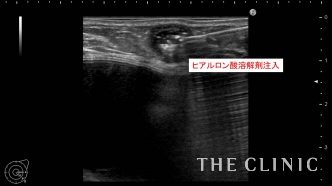

他院にてヒアルロン酸豊胸・バッグ豊胸を受けられ、その直後からしこりが触れはじめたとのこと。豊胸を受けたクリニックでは取り合ってもらえず、更に他院へ相談するがバッグが入っているため処置は難しいと言われ、当院を受診されました。 しこりの大きさは1cmですが、被膜を形成しています。

ヒアルロン酸のしこりのすぐ下にシリコンバッグ がありますのでバッグを損傷しないように注意する必要があります。 エコー下にて確実にヒアルロニダーゼをしこり内に注入し、その後ヒアルロン酸を吸引除去します。

吸引後、エコーにてしこりの消失を確認しました。 ヒアルロン酸のしこりはエコー下に行えば 、安全に確実に治療することが可能です。